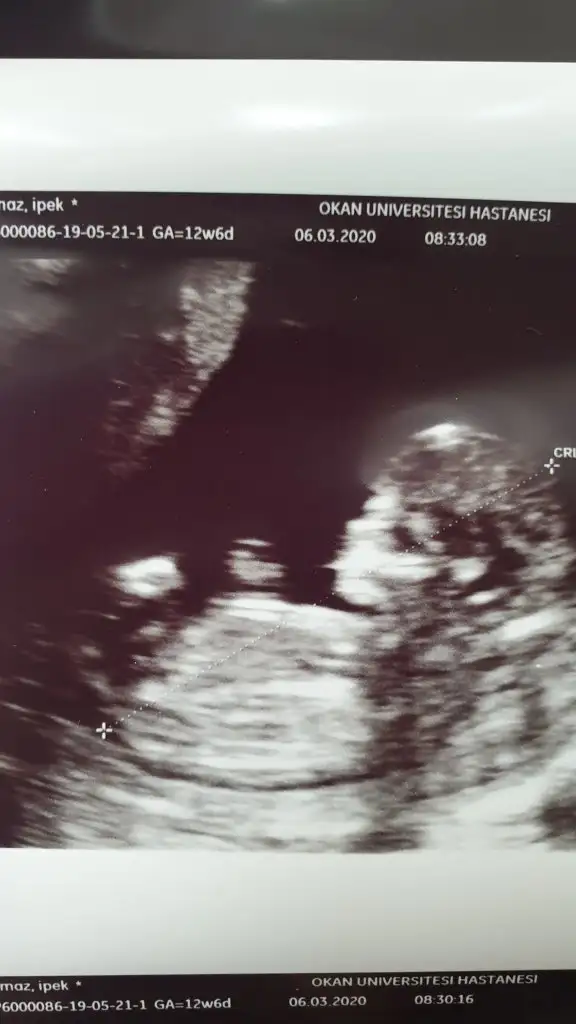

Erkek gibi 12+ yada 13 hafta paylaşınIkra meyra yorumunuzu alabilir miyim![]()

Tmm o zaman kontrole gidersek paylaşırım inşallahErkek gibi 12+ yada 13 hafta paylaşın